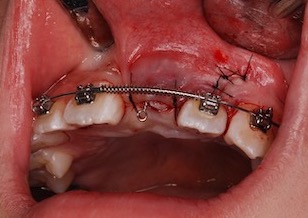

③準備が整ったところで口腔外科にて埋伏歯部の歯肉開窓(切開)を行っていただく。→埋伏歯の表面に矯正医がブラケットを装着する。(写真:BeforeⅣ)

④開窓(切開)した歯肉を復位・縫合していただく。(写真:After Ⅰ)